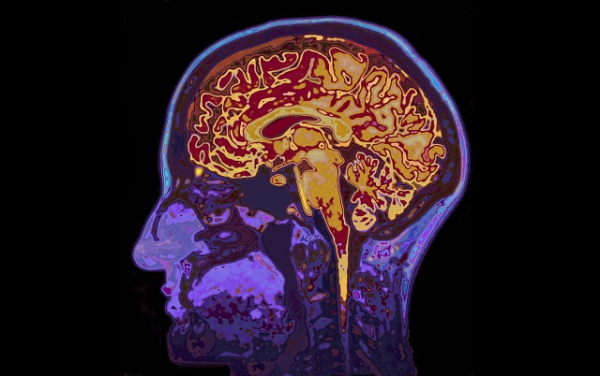

치매란 정상적으로 성숙한 뇌가 후천적인 외상이나 질병 등으로 외인으로 인하여 손상되거나 파괴되어 인지적인 기능에 다발성 장애가 생긴 것을 말합니다. 인지적인 기능이란 기억력, 이해력, 사고력, 계산능력, 학습능력, 언어 및 판단력 등을 포함하는 고도의 뇌피질 기능을 말합니다.

인지능력의 저하가 치매의 시작인 것입니다. 이러한 인지능력의 저하에 대한 증상들이 있는데요, 그것을 치매 초기증상 모습들로 발견할 수 있습니다. 이제 빨리 체크를 해 보셔야겠습니다. 치매 초기증상에 대해 자세히 적어놓을 테니 꼭 확인해 보시기 바랍니다.